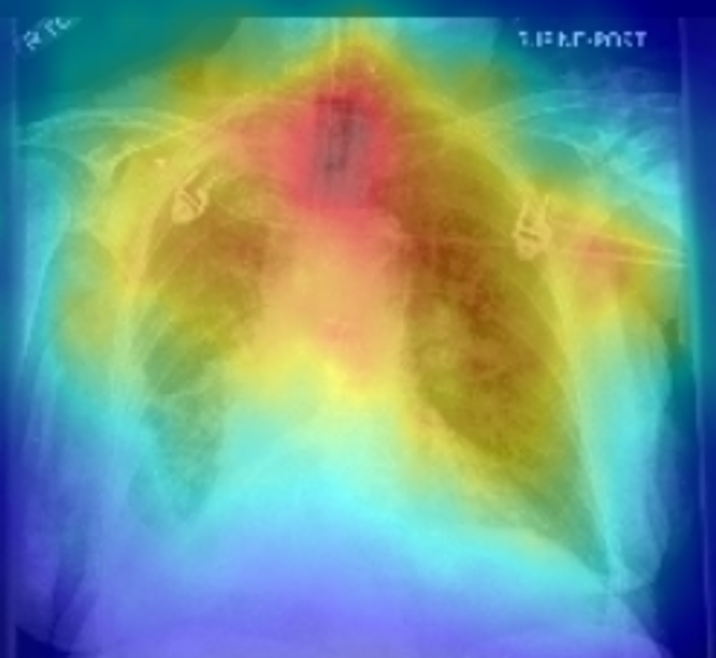

To delve deeper into the learned visual knowledge from IMITATE, we utilized Grad-CAM [57] to produce saliency maps for CXR images derived from the model in its pre-trained state. We select two CXR images showcasing two prevalent diseases, Edema and Lung Opacity. Notably, each of these images comes with ground truth annotation pinpointing the region of concern, as documented in [58]. As evident from Fig. 5, IMITATE boasts an impressive capability to accurately delineate the clinical regions of concern in the CXR images, outperforming its counterpart MGCA [4]. This is particularly noteworthy considering that IMITATE achieves this precision without relying on any external prompts or the need for additional model fine-tuning.